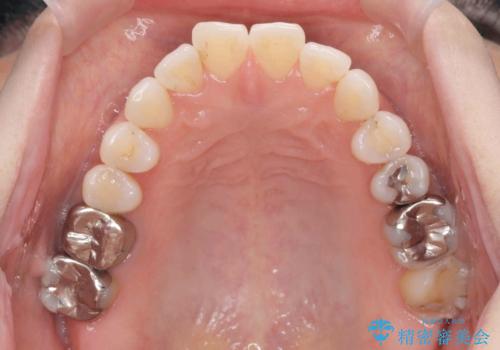

- 突き出た前歯の角度を改善したい、と矯正治療を希望され来院されました。

抜歯を行いワイヤー矯正で2-3年程度の時間をかけて、しっかり前歯を後方に移動させるか、

抜歯を行わずにIPR(歯の間に空隙を設ける)で可及的に角度の改善を行うか、

2通りの治療方針をご提案しました。

治療期間が約半年で行うことができ、歯を抜かずにマウスピース矯正で可及的に前歯の角度を改善する治療方針を

奥歯の状態等も鑑みて選択されました。

約半年で大きく前歯の角度を改善することができ、抜歯を行わない矯正治療の結果に大変喜んでいただくことができました。